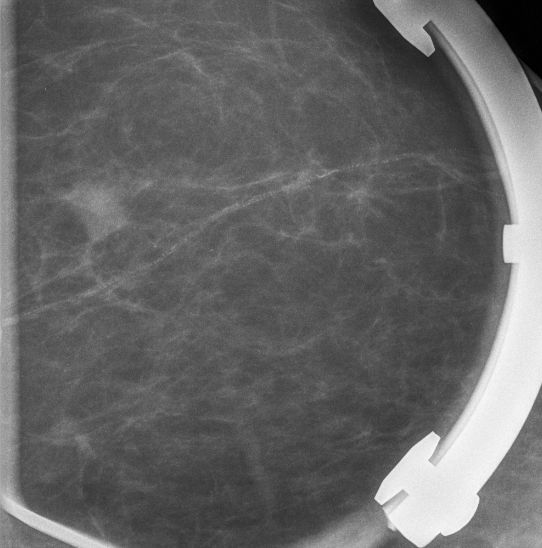

12mm großes invasives duktales Karzinom G3. Spotkompression.

| ||